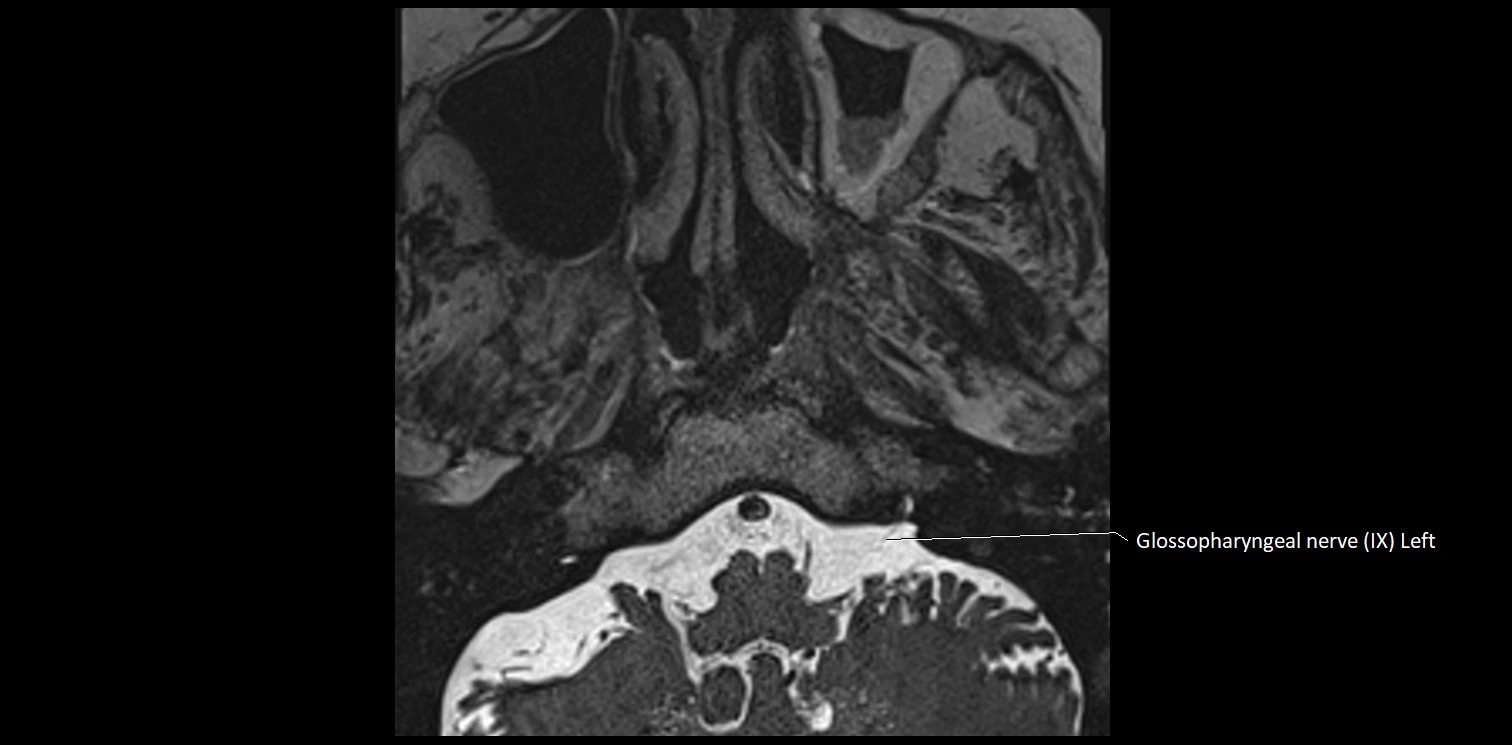

MRI images

image